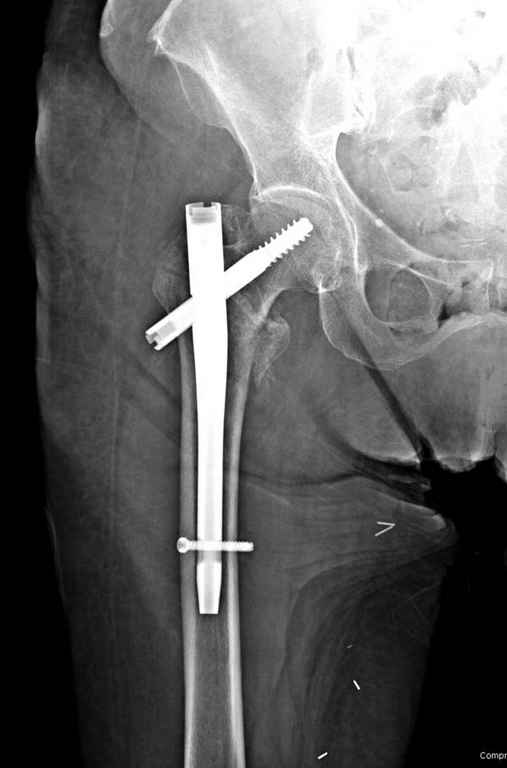

Фиксация * reversed obliquity* подвертельных переломов - дело непростое.

На мой взгляд, причиной телескопирования явилось несоответствие диаметра гамма нэйл с диаметром канала подвертельного отдела бедра: обратите внимание на величину протрузии шеечного винта и величину медиализации дистального фрагмента - они одинаковы, смещение или телескопирование фрагментов происходило до того момента, пока гамма нэйл не упёрся в медиальный кортекс и образовалось пространство между латеральным

кортексом и латеральной поверхностью гвоздя.